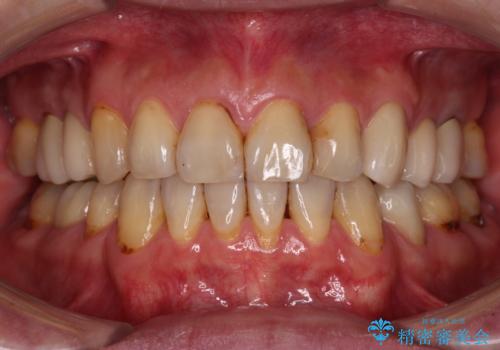

抜歯が必要と言われた前歯 根管治療とオールセラミッククラウン

根管治療を行った後にオールセラミッククラウンにて補綴することとしました。

初回の根管治療後には痛みが速やかに改善し、6か月後のレントゲン写真では根尖の病変が消失していることが確認できました。